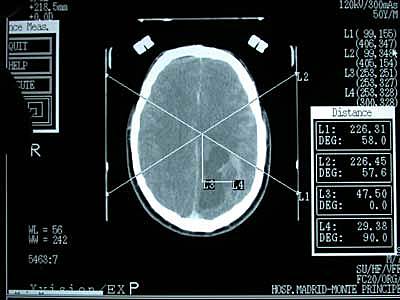

La primer cirugía fue realizada empleando un

neuronavegador que sobreponía reconstrucciones

tridimensionales de imágenes obtenidas por TAC

en el campo visual del microscopio, por Roberts y sus colaboradores